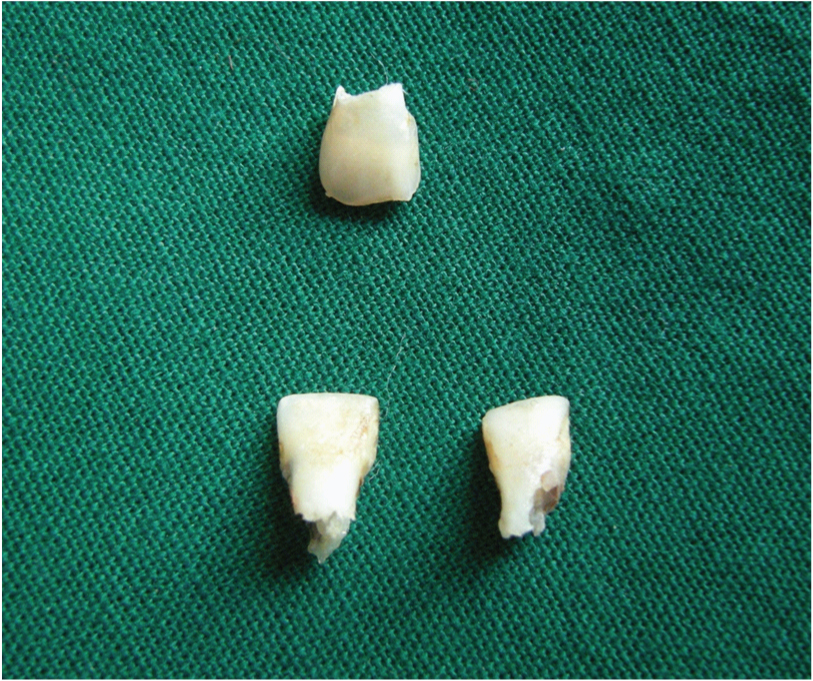

[Table/Fig-16] showing the resorption of the roots of the extracted teeth in relation to 12, 41 and 42. The teeth having mobility were extracted. The teeth 12, 41 and 42 were sent for histopathological examination (ground sectioning) which revealed: crown morphology comprising of enamel and dentin. The enamel shows striae of retzius, dentin showed dentinal tubules, interglobular dentin with an area resembling dead tract (longitudinal section). [Table/Fig-17] showing the ground section of the extracted tooth specimen. Followed by removable partial denture and teeth with resorped root was endodontically treated. Patient was advised to maintain proper oral hygiene and referred to the department of periodontology for further treatment of gingival enlargement and periodic follow up was suggested.

Showing the resorption of the roots of the extracted teeth in relation to 12, 41 and 42